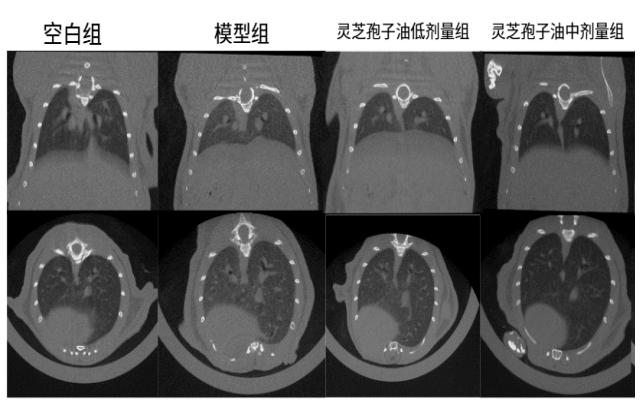

体内功效实验研究结果表明:在为期52天的小鼠实验中,每日6粒广药牌灵芝孢子油,灵芝孢子油显著减少了肺部肉芽肿结节的面积(减少23.07%)和磨玻璃阴影,降低炎症因子和趋化因子水平 ,证实广药牌灵芝孢子油具有一定的防治小鼠肉芽肿型肺结节的作用。

图:灵芝孢子油对肉芽肿型肺结节小鼠肺部断层扫描检测结果及统计

体内作用机制研究证实:通过调节PI3K-Akt-mTOR信号通路、抑制p-AKT和p-mTOR活化、纠正代谢紊乱、减少炎症因子和趋化因子的释放,最终达到缓解肉芽肿型肺结节的效果。